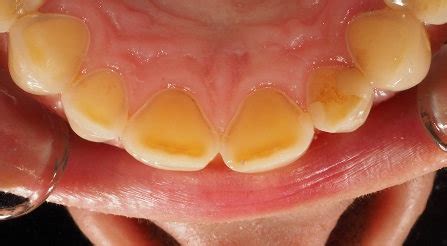

Los síntomas iniciales pueden incluir sensibilidad dental, cambio en la forma de los dientes y una apariencia amarillenta debido a la exposición de la dentina subyacente. La erosión dental afecta tanto a la salud oral como a la estética dental de manera significativa. Los dientes erosionados pueden sufrir problemas funcionales y presentar una apariencia más desgastada y decolorada, lo que impacta tanto en la salud bucal como en la autoestima y la calidad de vida de una persona.

El esmalte dental es la parte que recubre la parte externa de los dientes, cuya función es proteger la estructura interna del diente de los agentes patógenos externos, por ello, el debilitamiento del esmalte a causa de la erosión dental supone la exposición de la dentina (la parte de color amarillento del diente). Aunque la erosión dental puede pasar desapercibida en sus primeras fases, sus efectos a largo plazo pueden afectar tanto a la estética como a la funcionalidad de tu boca.

- Decoloración de los dientes: si se va dañando el esmalte debido a la erosión dental, el blanco natural de los dientes se va perdiendo, dando paso a un tono más amarillento. Cambios en la apariencia de los dientes: los dientes erosionados pueden cambiar su aspecto debido al debilitamiento del esmalte. Es decir, pueden adquirir una apariencia más fina y translúcida, especialmente en los bordes, así como volverse más cortos y desiguales.

- Desgaste de las piezas dentales: los dientes pueden llegar a cambiar de forma, verse más redondeados o aparecer pequeñas fisuras. También pueden aparecer ciertas transparencias en los bordes dentales, perdiendo estos su opacidad. Pérdida de estructura dental: la erosión avanzada puede provocar una pérdida significativa de la estructura dental, afectando a la forma y el tamaño de los dientes. Todo ello puede comprometer la función masticatoria, la alineación dental y la distribución de la fuerza al morder.